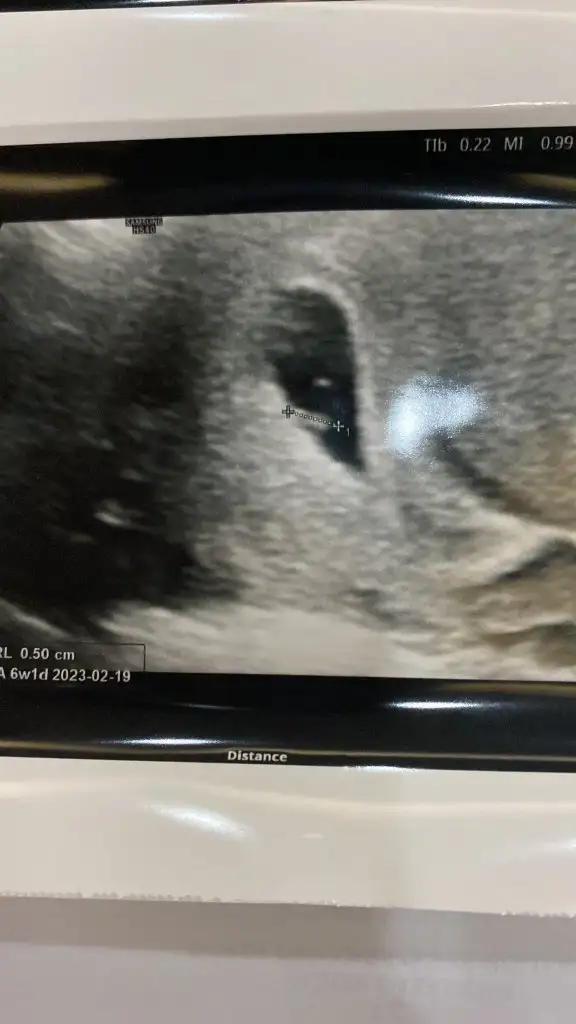

Merhaba 6 haftalık karından bakıldı. Yorumlarsanız sevinirim :) Pasha22 Pasha22

19,8 KB · Görüntüleme: 88